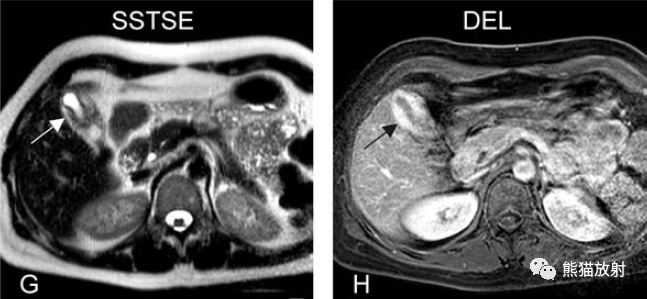

膽囊癌。病灶以膽囊為中心侵及肝臟,明顯彌散受限,由于病灶內(nèi)含結(jié)締組織/纖維成分(T2低信號(hào))導(dǎo)致肝被膜內(nèi)陷,增強(qiáng)掃描動(dòng)脈期明顯不均質(zhì)強(qiáng)化,延遲期中心纖維成分延遲強(qiáng)化。表現(xiàn)類(lèi)似肝內(nèi)膽管細(xì)胞癌。

膽囊壁增厚(并肝硬化、門(mén)脈高壓、腹水)。T2WI顯示膽囊壁因水腫而光滑均勻增厚,增強(qiáng)延遲期顯示強(qiáng)化的膽囊壁(內(nèi)外兩層:粘膜層和漿膜層),薄而清晰光滑。